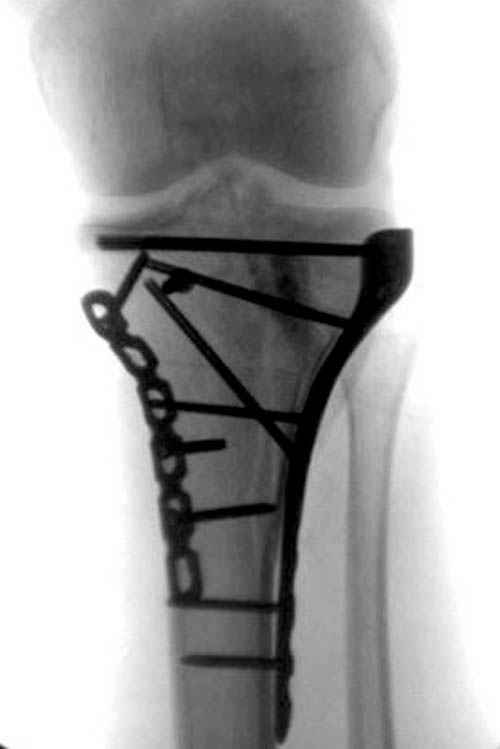

Трудно поверить, что разрекламированная Ортопедическая школа Восточной Украины позволяет такие странные снимки? На прямом снимке сохранен общий контур плато, но не известна судьба импрессии суставной поверхности. На полубоковой?, оставлен без репозиции задне-медиальный отдел, и навряд ли после такой фиксации можно удовлетвориться результатом.

Такая ситуация характерна для многих, когда принимается ошибочное решение, т.е пытаются фиксировать одним имплантом переломы двух мыщелков. Латеральная пластина приемлема только для тех случаев, когда сохраняется интактным медиальный диафизарный кортекс и отсутствует фрагментация на верхушке медиального перелома.

Здесь как раз тот случай, когда результат зависит не только от мастерства хирурга, но и от наличия современных методов исследования. Например, КТ которая поможет рассчитать направления шурупов и установку импланта. Кроме этого, поможет определиться с доступом.